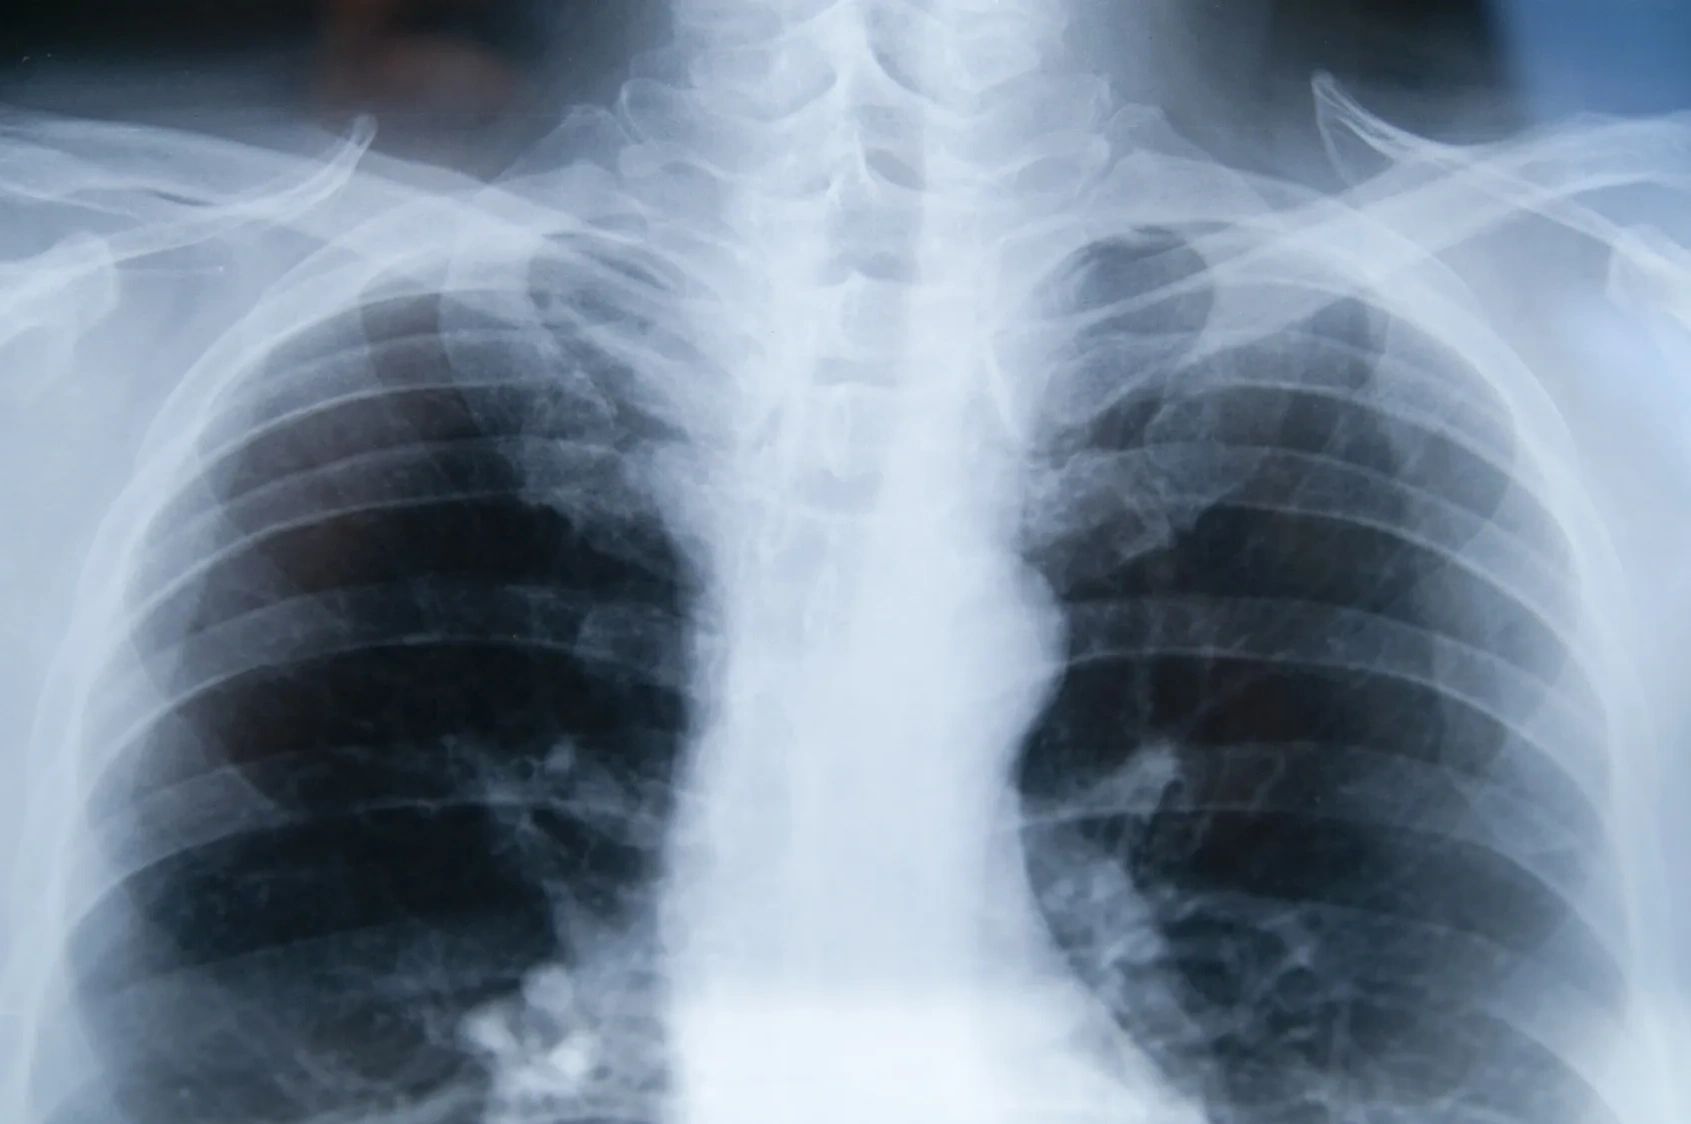

Medicolegal and expert witness reports for thoracic trauma, asbestos and thoracic cancers.